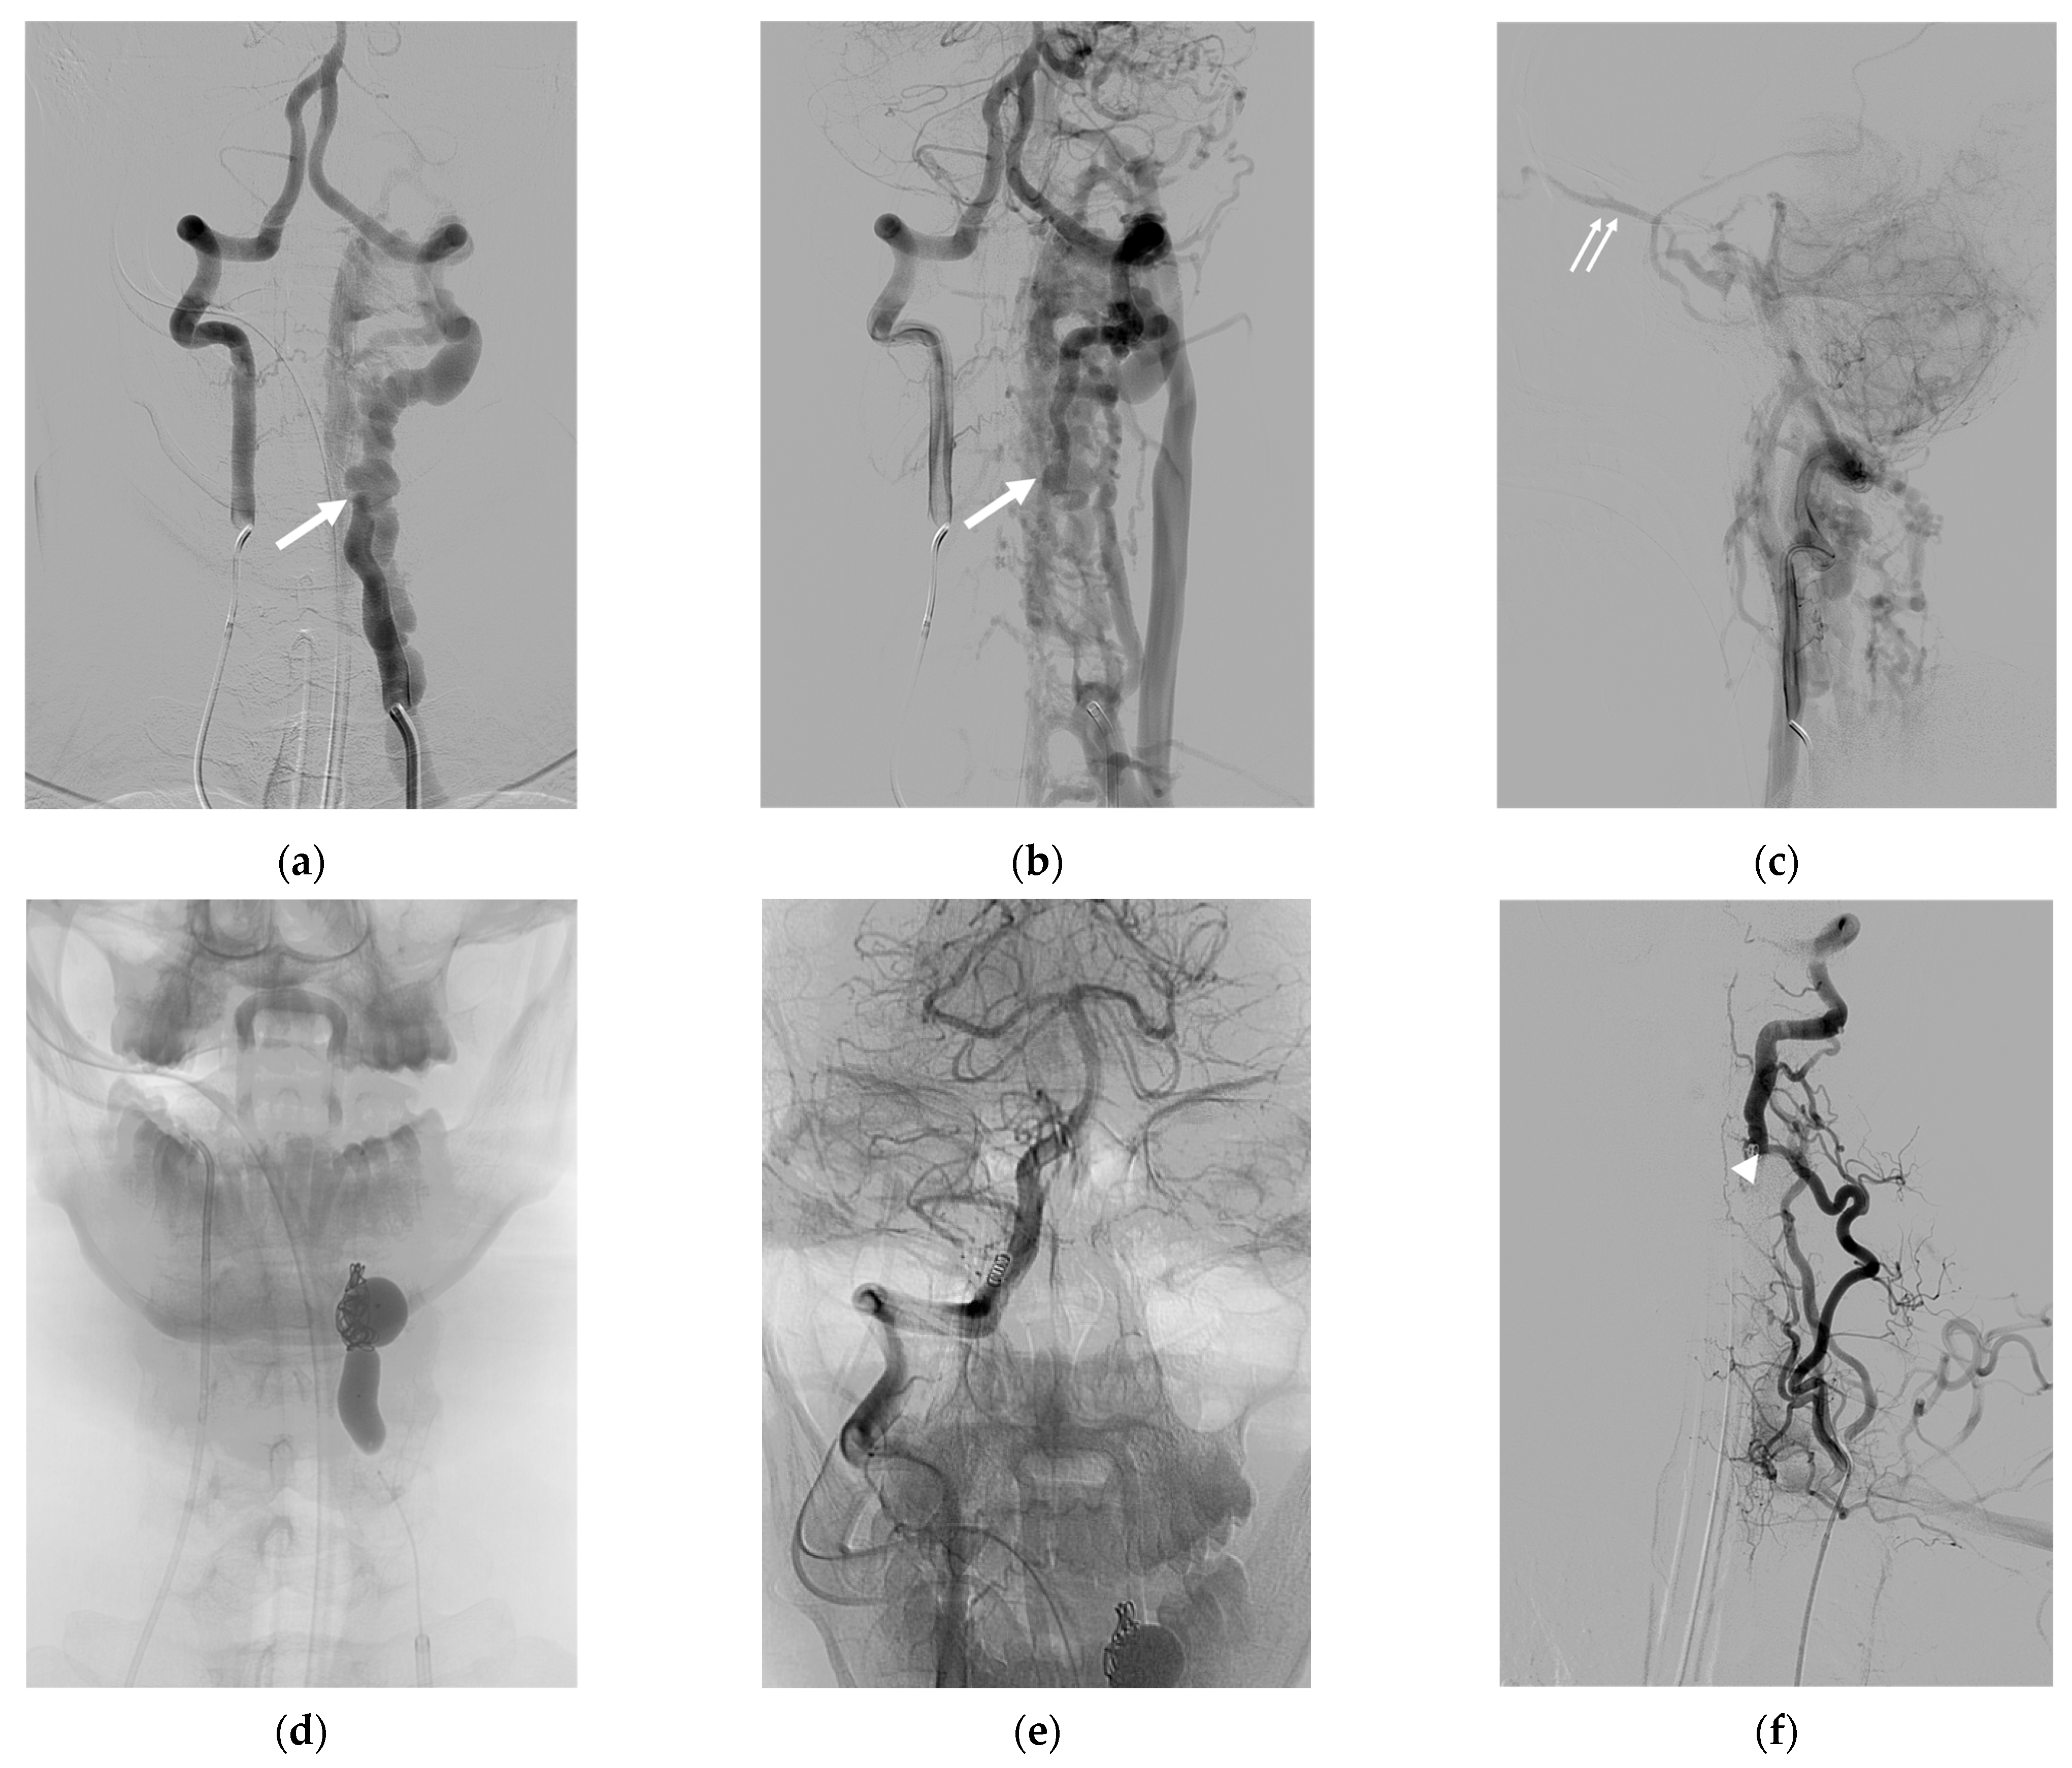

| 8 | F | 33 | Neck mass; tinnitus; paresthesia of left arm; ataxia | NF-1 | S | IJV; VVP with venous pouch | Y | B, C, and NBCA | O | Improved | Vertigo |

| 9 | F | 25 | Neck mass | NF-1 | S | VVP with venous pouch | Y | C and NBCA | O | Improved | None |

| 10 | F | 27 | Incidental finding | NF-1 | S | Lateral epidural vein with venous pouch | Y | NBCA | O | Improved | None |